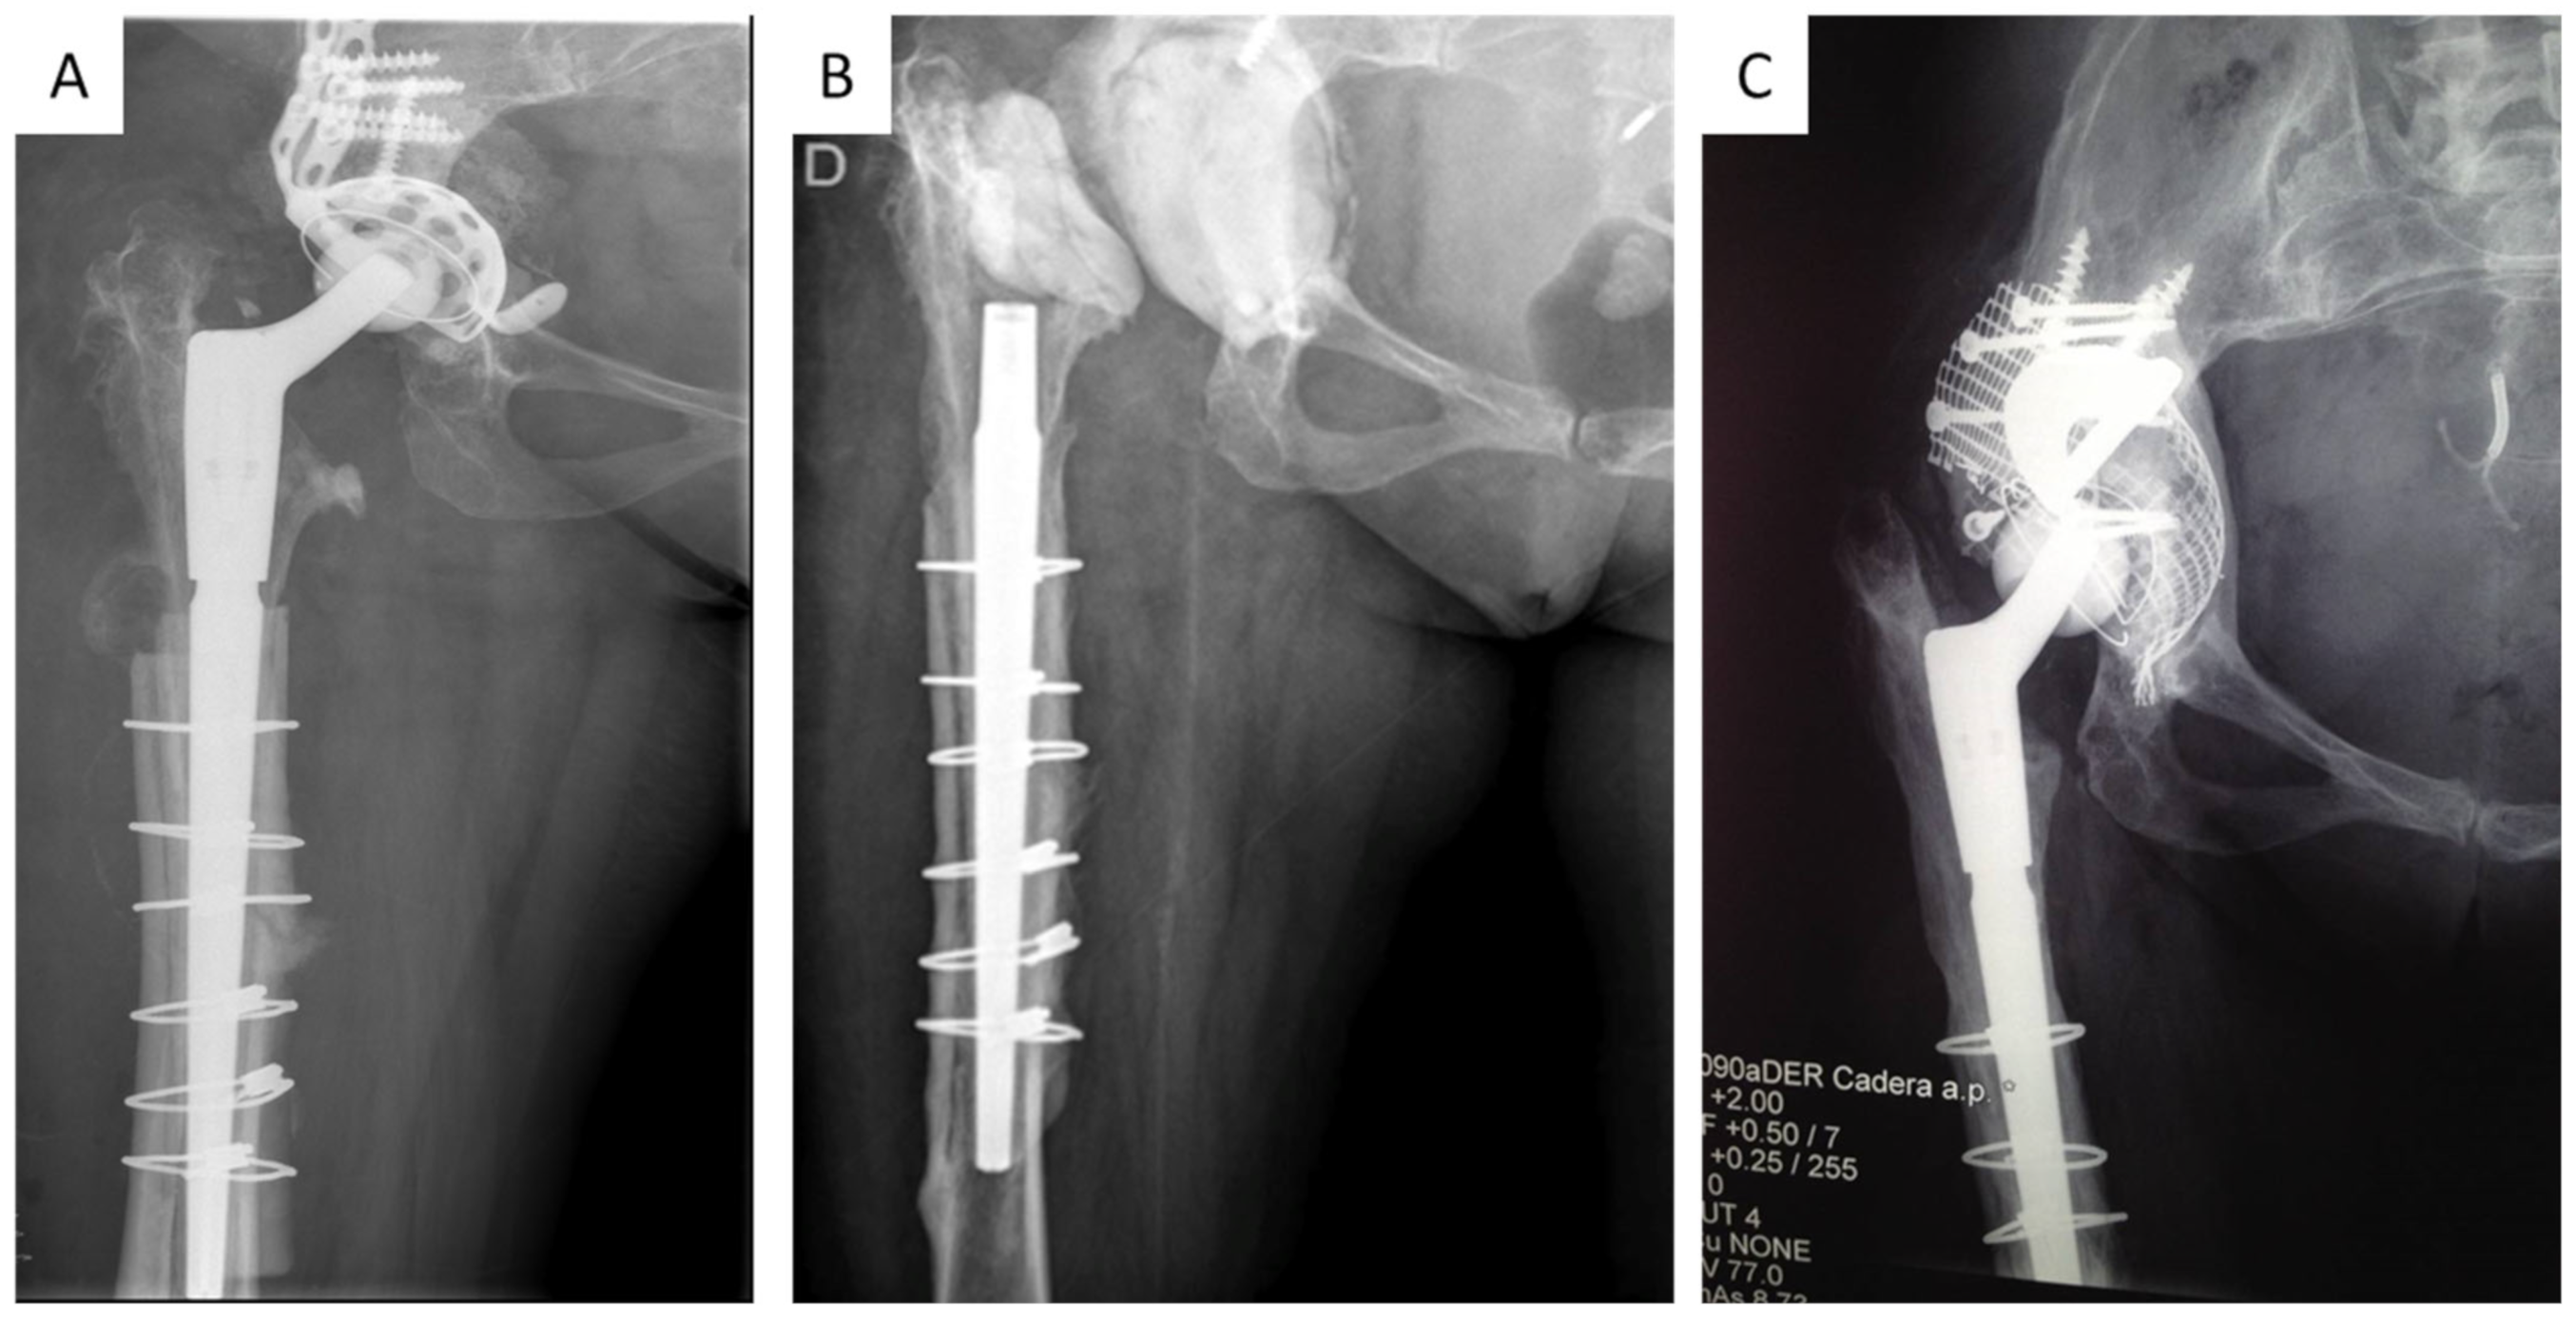

| Case | Preop X-ray Acetabular Loosening | Acetabular Defects [14] | Spacer | Acetabular Reconstruction | Antibiotics Therapy (Weeks) | Time to 2nd Stage (Weeks) | Postop Cultures | Follow-Up (Months) |

|---|---|---|---|---|---|---|---|---|

| 1 | + | IV | NA | TMT + B.I.G. | 8 | 20 | − | 132 |

| 2 | + | V | NA | PLATE + CUP–CAGE | 8 | 10 | − | 84 |

| 3 | − | II | A | REVISION SHELL | 8 | 16 | − | 96 |

| 4 | + | V | A | PLATE + CUP–CAGE | 8 | 64 | − | 84 |

| 5 | − | II | A | REVISION SHELL | 8 | 12 | − | 48 |

| 6 | + | IV | NA | PLATE + CUP–CAGE | 8 | 44 | − | 84 |

| 7 | − | IV | NA | REVISION SHELL + TMT | 8 | 12 | − | 36 |

| 8 | − | II | NA | REVISION SHELL | 8 | 10 | − | 24 |